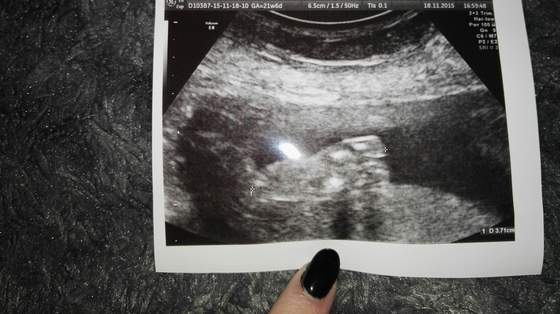

Mordka się śmieje od rana, aż chęci do życia wróciły ;-)a mnie dzisiaj wzięło, żeby obejrzeć nasze wesele....podziele się z wami jednym z naszych teledysków ślubnych https://www.youtube.com/watch?v=3EVk-B5we9w&feature=youtu.be wciąż nie mogę uwierzyć, ze 2,5 roku czekalismy na ten ślub... tyle przygotowań a to tak przeleciało.... i od razu po ślubie dzidzia <3